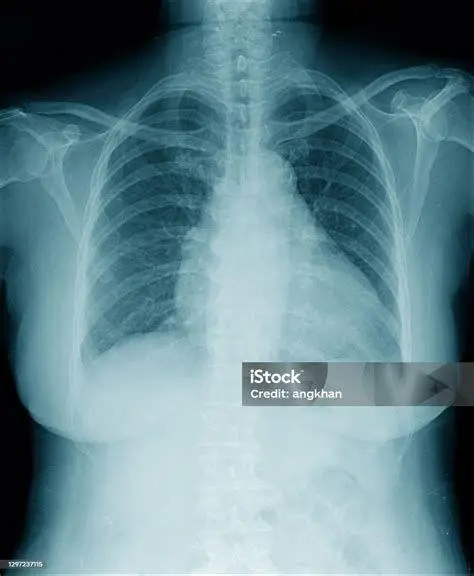

Ketika pasien datang dengan keluhan pernapasan, dokter spesialis paru biasanya akan melakukan serangkaian pemeriksaan diagnostik untuk memastikan adanya infeksi paru paru. Langkah awal dimulai dengan auskultasi menggunakan stetoskop untuk mendengarkan suara napas yang tidak normal, seperti suara crackles atau wheezing.

Pemeriksaan penunjang yang sering dilakukan meliputi rontgen dada (X-ray Thorax) untuk melihat lokasi peradangan atau adanya efusi pleura (cairan di selaput paru). Selain itu, pemeriksaan darah lengkap diperlukan untuk melihat peningkatan jumlah sel darah putih (leukosit) sebagai tanda adanya infeksi aktif. Dalam kasus yang lebih kompleks, CT scan atau bronkoskopi mungkin diperlukan untuk mengambil sampel jaringan atau cairan paru guna identifikasi patogen secara lebih spesifik melalui uji kultur.